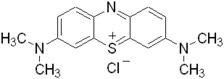

| Structure du bleu de méthylène. | ||

Le bleu de méthylène, ou chlorure de méthylthioninium, est un composé hétérocyclique à trois noyaux dérivé de la phénothiazine utilisé à la fois comme médicament et colorant dont l'action repose sur les propriétés rédox. Il a été préparé pour la première fois par Heinrich Caro en 1876[5]. C'est un solide cristallisé inodore soluble dans l'eau et, dans une moindre mesure, dans l'éthanol. À l'état pur, il se présente sous la forme d'une poudre vert foncé ; on le trouve commercialement également sous forme d'un sel double avec le chlorure de zinc, de couleur brune.